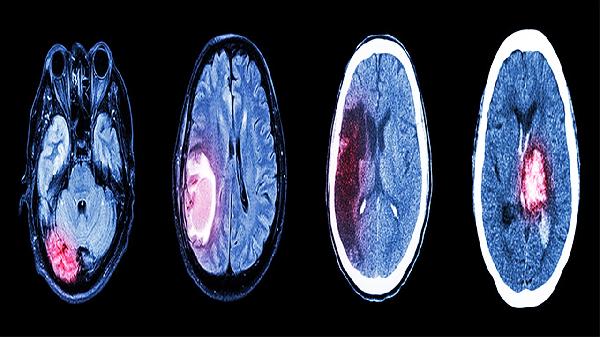

头CT或MRI可排除脑肿瘤、脑积水、脑血管病变等可能引起类似痴呆症状的疾病。这些器质性疾病导致的认知功能障碍与阿尔茨海默病的治疗方案不同,影像学检查有助于明确诊断方向。

阿尔茨海默病特征性的内侧颞叶萎缩可通过MRI清晰显示,海马体积测量已成为重要的辅助诊断指标。CT虽分辨率较低,但仍可观察脑室扩大等间接征象,为病情评估提供客观依据。

不同痴呆类型的脑部改变各有特点,如路易体痴呆的枕叶代谢减低、血管性痴呆的多发梗死灶等。影像学特征结合临床表现可提高诊断准确性,避免误诊误治。